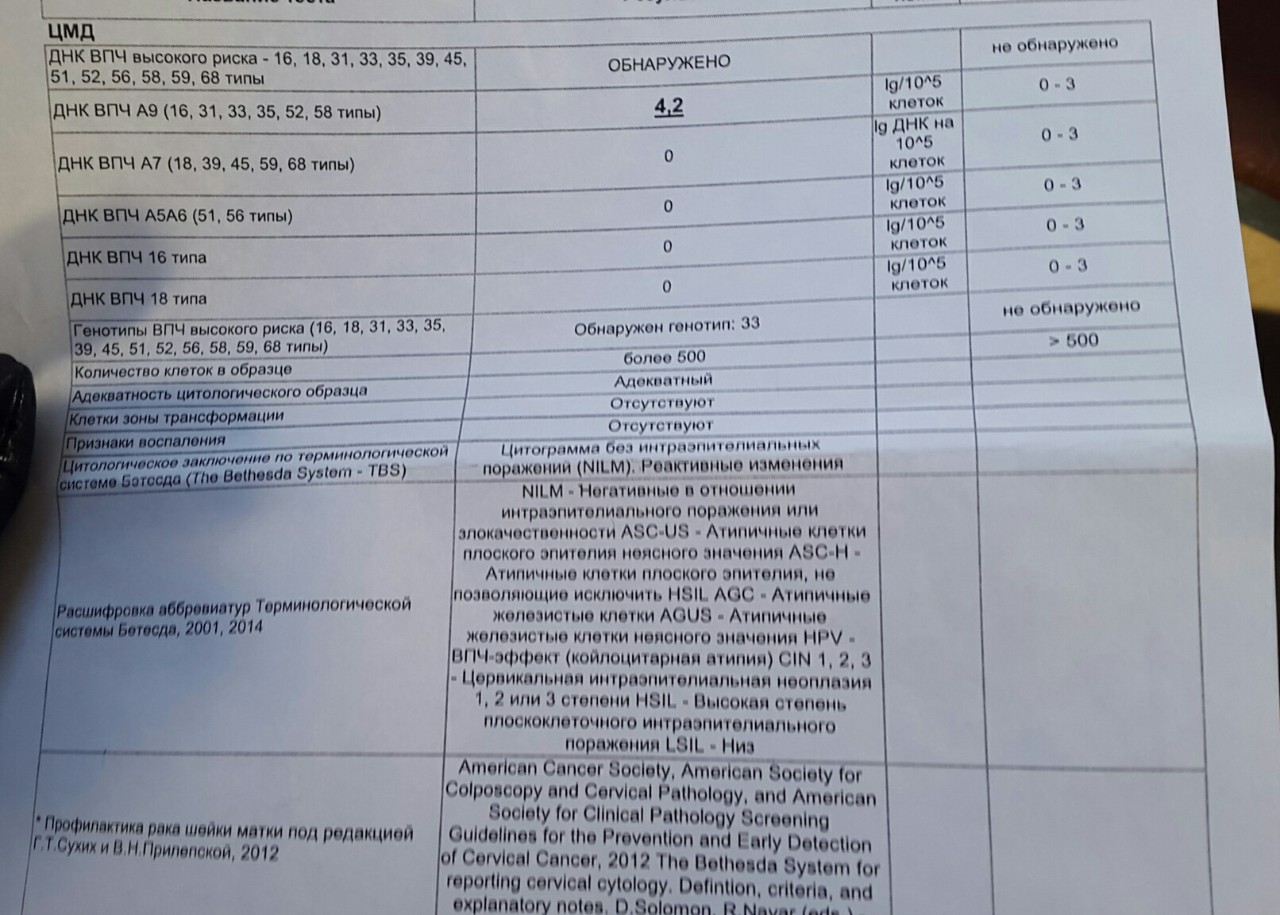

Кондиломы - это одно из самых распространенных заболеваний, передающихся половым путем. Они вызваны вирусом папилломы человека (ВПЧ) и могут появляться на внешних половых органах, анусе, ротовой полости и других областях тела.

Симптомы кондилом могут варьироваться, и визуальное представление этого заболевания может быть различным. Некоторые кондиломы выглядят как небольшие бугорки или бородавки, в то время как другие могут иметь форму плоских пятен или цветных наростов.